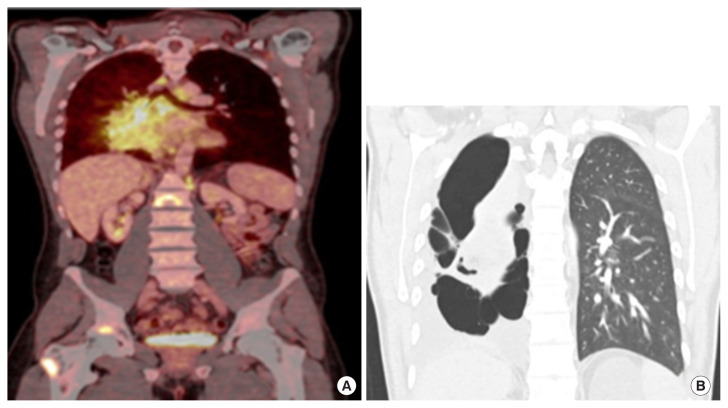

约3%至5%的间变性淋巴瘤激酶(ALK)基因发生致癌重排的个体发展为非小细胞肺癌(NSCLC)。Brigatinib是一种有效的下一代ALK酪氨酸激酶抑制剂(TKI),已显示出显着的全身和颅内反应,以及改善的无进展生存期,具有可接受的安全性。根据欧洲肿瘤医学学会指南,ALK易位和性能状态为0-3的患者可以接受TKI(布加替尼、阿勒替尼或氯拉替尼)一线治疗。据我们所知,这是第一例布加替尼增加剂量后肺部出现囊性或大泡性变化的报道。在这里,我们描述了一个37岁的男性,从不吸烟,在接受布加替尼治疗肺内转移的非小细胞肺癌时,肺实质出现渐进性弥漫性囊性改变。临床医生应该对这种潜在的非典型肺不良反应保持警惕,包括肺实质囊性或大泡性转化的可能性。

Approximately 3% to 5% of individuals with oncogenic rearrangements in the anaplastic lymphoma kinase (ALK) gene develop non-small cell lung cancer (NSCLC). Brigatinib, a potent next-generation ALK tyrosine kinase inhibitor (TKI), has demonstrated significant systemic and intracranial responses, as well as improved progression-free survival, with an acceptable safety profile. According to European Society for Medical Oncology guidelines patients with ALK translocation and performance status 0-3 can be offered 1st line treatment with TKI (brigatinib, alectinib, or lorlatinib). To our knowledge, this is the first reported case of cystic or bullous changes in the lungs following incremental dosing of brigatinib. Here, we describe a 37-year-old male, a never-smoker, who developed progressively diffuse cystic changes in the lung parenchyma while receiving brigatinib treatment for NSCLC with intrapulmonary metastases. Clinicians should remain vigilant for this potential atypical pulmonary adverse effect, including the possibility of cystic or bullous transformations in the lung parenchyma.